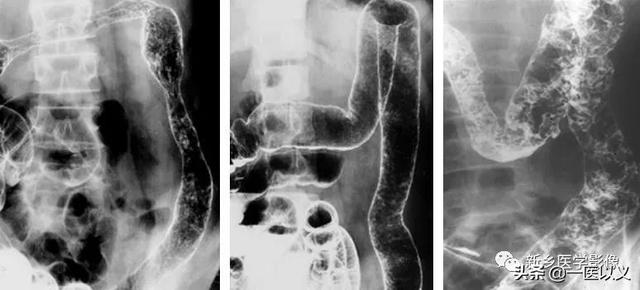

Der Bariumeinlauf spielt eine wichtige Rolle bei der Diagnose von Patienten mit mittelschwerer bis fortgeschrittener Colitis ulcerosa.Es können Ödeme und Ulzerationen der Darmschleimhaut festgestellt werden.

Diagnosekriterien für Colitis ulcerosa: ① Ausschluss von bazillärer Dysenterie, Amöbenkolitis, Schistosomiasis, Darmtuberkulose, Morbus Crohn, Strahlenenteritis und anderen Ursachen für eine Entzündung des Dickdarms; ② typisches klinisches Bild und zumindest endoskopische oder röntgenologische Darstellung der charakteristischen Veränderungen von 1; ③ klinische Symptome sind nicht typisch, aber es gibt eine typische Koloskopie oder Röntgenaufnahme oder Biopsie der Pathologie zur Bestätigung der